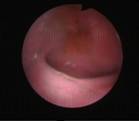

The commonly misleading history given by the parents is that the child may have had a trivial trauma or an insect bite. However, for the clinician the golden rule should be ‘Any acute scrotum is testicular torsion unless proved otherwise’. Investigations like ultrasound and color doppler may be done to help in the diagnosis. However, in the event of any doubt, it is safest to do a surgical exploration of the scrotum. The other uncommon causes of acute scrotum are acute epidydymo orchitis, scrotal abscess, idiopathic scrotal oedema and torsion of appendix of the testis. ●